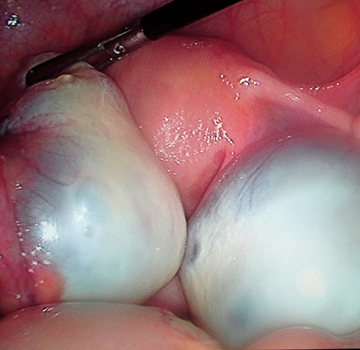

Stones in the gallbladder